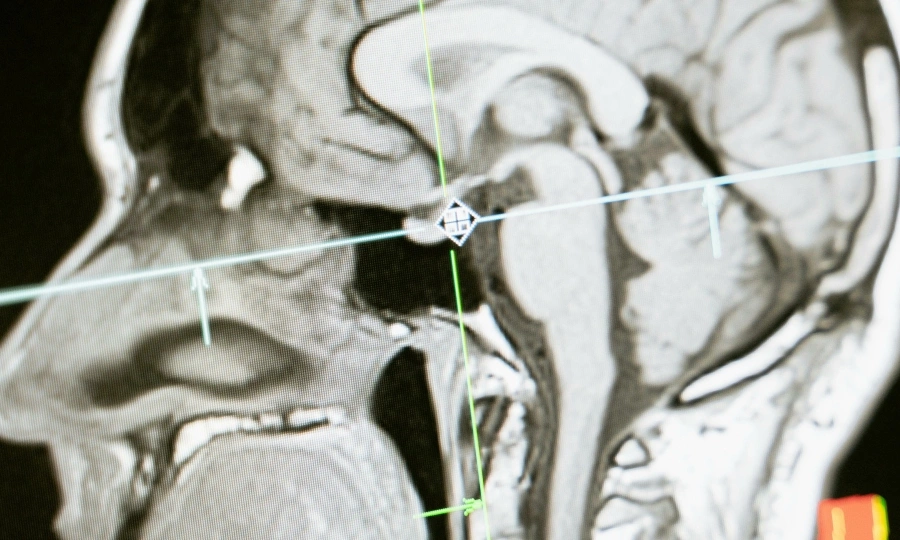

Doctors in Hanoi say a 15-year-old boy has suffered severe brain damage after vaping an e-cigarette laced with synthetic drugs he bought online.